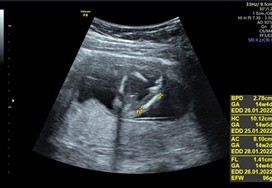

14w รบกวนเเม่ๆช่วยดูหน่อย ญ หรือ ช ค่ะ